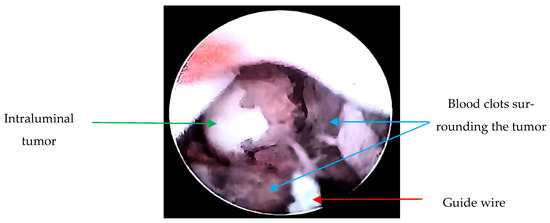

Due to the suspicion of a urothelial tumor, the patient underwent diagnostic cystoscopy and ureteroscopy; during the procedure, a biopsy was taken (Figure 2). Using interventional radiology, it was decided to drain the abscessed liver tumor, obtaining purulent fluid. The drained fluid from the liver abscess was inoculated into liquid thioglycolate medium (Bioxon) and incubated for 24–48 h, then subcultured in BD Bactec™ Plus Aerobic/F and BD Bactec™ Anaerobic/F culture vials, replated, and incubated in a reducing environment; however, no isolation of Actinomyces spp. was obtained.

Figure 2.

Ureteroscopy: Endoscopically, a guide wire (red arrow) and a tumor dependent on the lumen of the right ureter in the lower third with obstruction (green arrow) are observed. Additionally, blood clots surrounding the tumor are visualized (blue arrows). Upon passage of the guide wire, pyuria is noted due to the tumor causing complete obstruction, resulting in a foggy appearance.